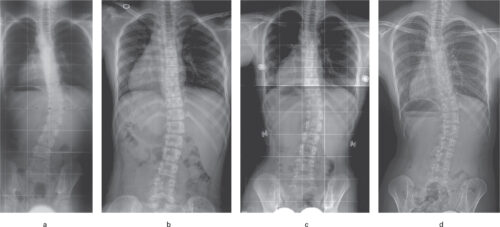

أُجريت دراسة حديثة على 207 مراهقين مصابين باعوجاج العمود الفقري مجهول السبب، وكان متوسط أعمارهم حوالي 12.8 سنة.

تمت متابعة المرضى منذ بداية ارتداء الحزام وحتى انتهاء فترة العلاج، لتحديد العوامل التي تؤثر في نجاح العلاج بالحزام، ومقارنة النتائج بمؤشر SCI.

أظهرت الدراسة نتائج واضحة ومبشرة يمكن تلخيصها في النقاط التالية:

كلما زادت مرونة العمود الفقري قبل ارتداء الحزام (أكثر من 18%)، كانت فرصة نجاح العلاج أفضل.

فالمرونة العالية تعني أن العمود الفقري يمكن تصحيحه بسهولة أكبر بالحزام.إذا حقق الحزام تصحيحًا أوليًا بنسبة تفوق 28.8%، فإن احتمالية تدهور الانحناء تقل بشكل واضح.

عندما تكون قيمة مؤشر SCI أكبر من 1.21، تنخفض احتمالية الحاجة إلى جراحة لاحقًا بشكل كبير.

حتى عند مراعاة العوامل الأخرى مثل العمر، نوع الانحناء، ومرحلة النمو العظمي، ظل مؤشر SCI أحد أقوى المؤشرات الدالة على نجاح العلاج بالحزام.

فبدلًا من الاعتماد فقط على التقديرات أو الفحص البصري، يمكن للطبيب الآن الاعتماد على أرقام دقيقة تُقاس من خلال الأشعة.

إجراء أشعة في وضع الاستلقاء لتحديد مرونة العمود الفقري.

إجراء أشعة أثناء ارتداء الحزام لمعرفة نسبة التصحيح الفعلية.

حساب مؤشر SCI لتقييم فعالية الحزام قبل بدء العلاج الكامل.